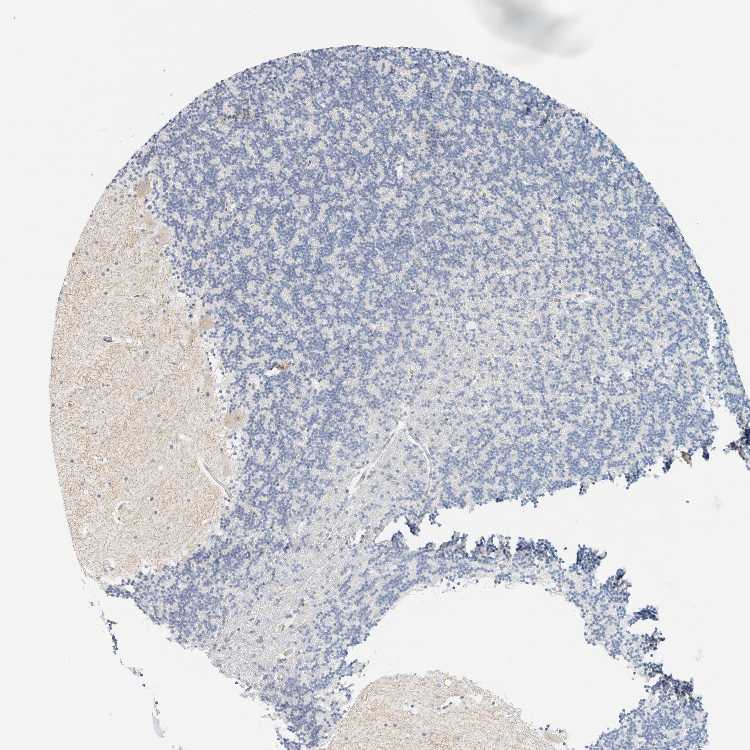

CEREBELLUM - Antibody stainingi

Antibody staining in the annotated cell types in the current human tissue is reported as not detected, low, medium, or high, based on conventional immunohistochemistry profiling in selected tissues. This score is based on the combination of the staining intensity and fraction of stained cells.

Each image is clickable and will lead to virtual microscopy that enables deeper exploration of all samples and also displays staining intensity scores, fraction scores and subcellular localization as well as patient and tissue information for each sample.

Antibody HPA024107

Purkinje cells Not detected

Cells in granular layer Not detected

Cells in molecular layer Not detected